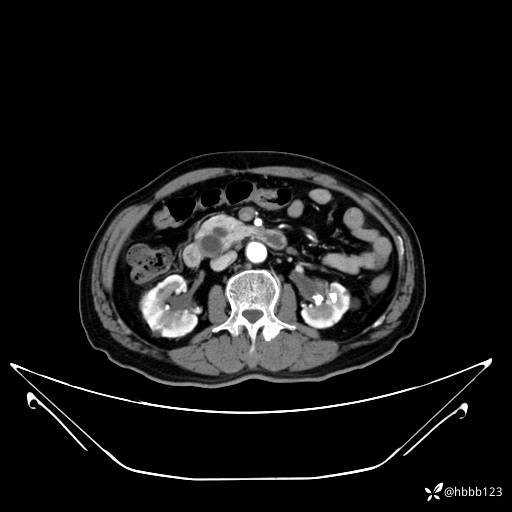

动脉期: